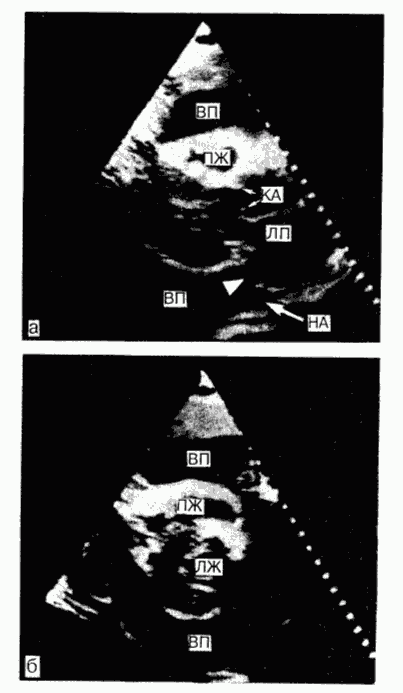

Эхокардиография: Диагностика перикардиального выпота Эхокардиография - наиболее эффективный и доступный метод диагностики, обладающий достаточной чувствительностью и специфичностью, простой в выполнении, неинвазивный, безвредный; может быть выполнен у постели больного. При наличии небольшого выпота в перикарде выявляется относительно свободное от эхо-сигнала пространство между задней частью перикарда и задней частью эпикарда левого желудочка. При большем объеме выпота это пространство располагается между передней частью перикарда правого желудочка и париетальной частью перикарда непосредственно под передней грудной стенкой (рис. 194-1). У больных со значительным выпотом сердце может свободно колебаться внутри перикардиального мешка, при значительной выраженности процесса это движение может вызвать нарушение электрической функции сердца. Несмотря на то что выполнение эхокардиограммы в М-режиме обычно достаточно для установления наличия выпота в перикарде, двухмерная эхо-кардиограмма более информативна, поскольку позволяет точнее локализовать процесс и количественно оценить объем жидкости в перикарде. При наличии тампонады во время вдоха наблюдается увеличение диаметра правого желудочка и уменьшение диаметра левого желудочка и диаметра левого предсердно-желудочкового (митрального) клапана при его открытии. Часто регистрируется позднее диастолическое движение внутрь (коллапс) свободной стенки правого желудочка и правого предсердия. Диагноз наличия жидкости в перикарде или его утолщения может быть подтвержден одним из следующих методов.1. Катетеризация сердца. Катетер проводят в правое предсердие и поворачивают таким образом, чтобы его конец вошел в контакт с латеральной стенкой правого желудочка. При наличии выпота или утолщения перикарда конец катетера отделен от рентгеноконтрастных легких непрозрачной полосой. 2. Ангиокардиография. Контрастное вещество быстро вводят в правое предсердие, и в этом случае латеральная стенка отделена от края сердечного силуэта. В тех случаях, когда считают необходимым удалить перикардиальную жидкость с диагностическими или лечебными целями, иглу, прикрепленную к правильно заземленному ЭКГ-отведению, вводят в перикардиальное пространство, при этом обычно используют субксифоидальный доступ. До того как жидкость будет удалена, следует измерить интраперикардиальное давление. С появлением выпота жидкость почти всегда приобретает признаки экссудата. При туберкулезе или опухолях жидкость имеет геморрагический характер, однако это может быть характерно и для выпота, сопровождающего ревматическую лихорадку или синдром посттравматического повреждения сердца (см. ниже). Изредка геморрагическая жидкость появляется в экссудате при уремическом перикардите, а также при гемоперикарде, развившемся после инфаркта миокарда, особенно в случае применения антикоагулянтов. ![]() Рис. Двухмерное изображение и изображение из парастернальной области систолы у больного со значительным выпотом в перикарде, окружающем все сердце. Стрелками указано распространение жидкости за левое предсердие и вперед в область нисходящей грудной аорты, а - двухмерное изображение; б - изображение в коротком размере. Обозначения: НА- нисходящая аорта; КА - клапан аорты; ЛП - левое предсердие; ЛЖ - левый желудочек; ВП - выпот в перикарде; ПЖ - правый желудочек (с изменениями из PC Come (Ed). Diagnostic Cardiology: Noninvasive imaging techniques. - Philadelphia, Lippincott 1985) |